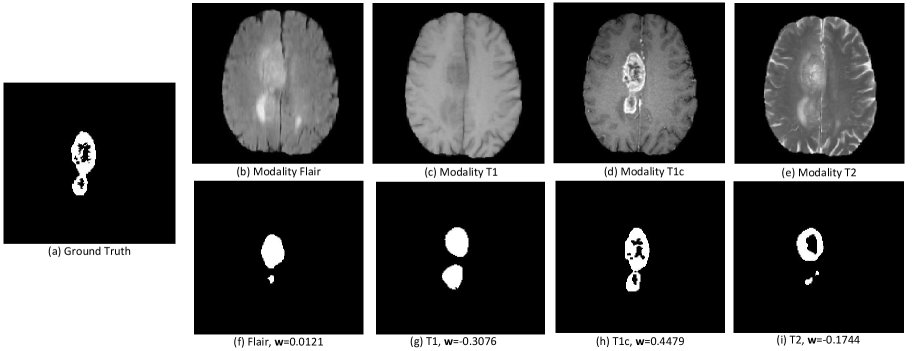

Figure 1: Visualization of the enhancing tumor (ET) segmentation results from each modality on a BraTS2018 image. Sub-figure (a) shows the Ground Truth segmentation; (b)-(e) and (f)-(i) display the original modalities (Flair, T1, T1c or T2) and their segmentations, along with the importance weights (𝐰\mathbf{w} in the legend) learned automatically (before normalization) by our MetaKD. Note that as the importance weight increases, segmentation accuracy improves. This insight enables the development of our meta-learning approach that automatically distills knowledge from higher-accuracy modalities to those with lower accuracy, enhancing overall model performance.

In this paper, we propose a novel method called Meta-learned Modality-weighted Knowledge Distillation (MetaKD) for multi-modal learning with missing modalities designed to handle the performance and task adaptation challenges mentioned above. MetaKD leverages meta-learning to automatically estimate modality importance weights and distill knowledge from the most “important” modalities. An example is shown in Fig. 1, where higher segmentation accuracy is automatically associated with a larger importance weight by MetaKD. The learned importance is adopted to weight the knowledge distillation terms to distill information from modalities with higher importance to those with lower importance. In addition, MetaKD is adaptable to multiple tasks, such as classification and segmentation. Our main contributions are: